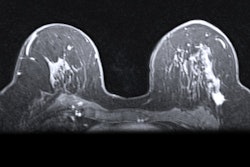

The COVID-19 vaccine appears to increase incidence of axillary lymphadenopathy on breast MRI -- thus boosting women's risk of unnecessary biopsy, according to a study published February 5 in the American Journal of Roentgenology.

"Early clinical experience with coronavirus disease (COVID-19) vaccination suggests that the approved COVID-19 vaccines cause a notably higher incidence of axillary lymphadenopathy on breast MRI compared to other vaccines," the group wrote. "Guidelines are needed to appropriately manage MRI-detected unilateral axillary lymphadenopathy in the era of COVID-19 vaccination and to avoid biopsies of benign reactive nodes."

If lymphadenopathy is discovered in patients who have received the COVID-19 vaccine, the team suggests categorizing it as BI-RADS 3 and recommending a follow-up ultrasound six to eight weeks after the second vaccine dose.